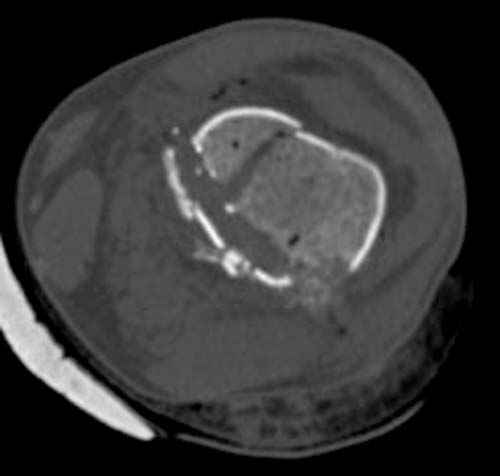

У молодого человека огнестрельное слепое ранение н/3 правого бедра. Поступил в клинику с внутрисуставным многооскольчатым Т-отразным переломом дистального отдела бедренной кости. Дополнительно на СТ-исследовании обнаружен перелом внутреннего мыщелка Hoffa со смещением.

Больной взят в операционную на второй день, где из небольшого медиального доступа выполнена артротомия коленного сустава. Произведена репозиция отломков, фиксация винтами. Попутно удалена пуля. Первым делом была достигнута репозиция медиального мыщелка (перелома Hoffa, где коронарная плоскость перелома трудно поддается закрытой репозиции и фиксации. ) Затем была достигнута идеальная репозиция суставной поверхности бедра и фиксация компрессирующими headless screws.

Дистальный отдел бедра был дополнительно фиксирован buttress пластиной с медиальной стороны из того же разреза. Для усиления фиксации латеральной колонны - с латеральной стороны закрытым способом из минидоступа установлена еще buttress plate. Пулевой канал дополнительно не подвергался хирургической обработке.